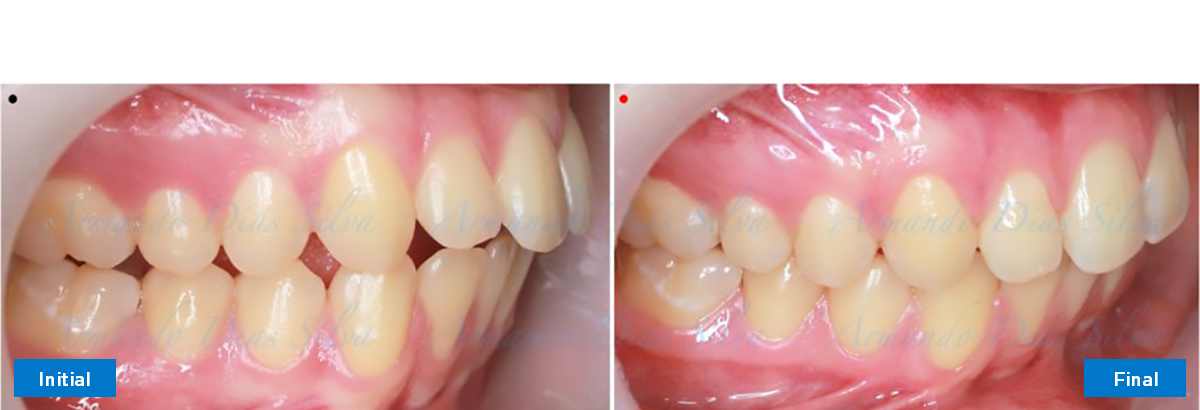

Clase II, Div. 1: Protrusión del incisivo central y espacios anteriores (SureSmile® Aligners)

Principal queja del paciente: Protrusión del incisivo central y mordida abierta. El paciente rechaza la expansión del arco palatino (MARPE) y las extracciones.

Este paciente adolescente presenta molares de Clase II y no le gusta su mordida abierta ni lo protrusivos que son sus dientes frontales. Por sus fotografías faciales, parece que su mandíbula es retrognática o le falta volumen en la barbilla. El historial del paciente también indica que existe un problema funcional al no haber guía de los incisivos.

Diagnóstico

• Molares de clase II

• El primer molar superior derecho está en una posición más mesial que el primer molar superior izquierdo

• Incisivos superiores e inferiores proclinados

• Desrotar y distalizar los molares superiores

• Retruir los incisivos superiores

Se logran todos los objetivos principales:

• Molares de clase I logrados con distalización y sin elásticos

• Sin cambios en la posición del cóndilo

• Sin expansión maxilar, respetando la envoltura periodontal

• Incisivos inferiores retroinclinados, que mejoran la estabilidad a largo plazo